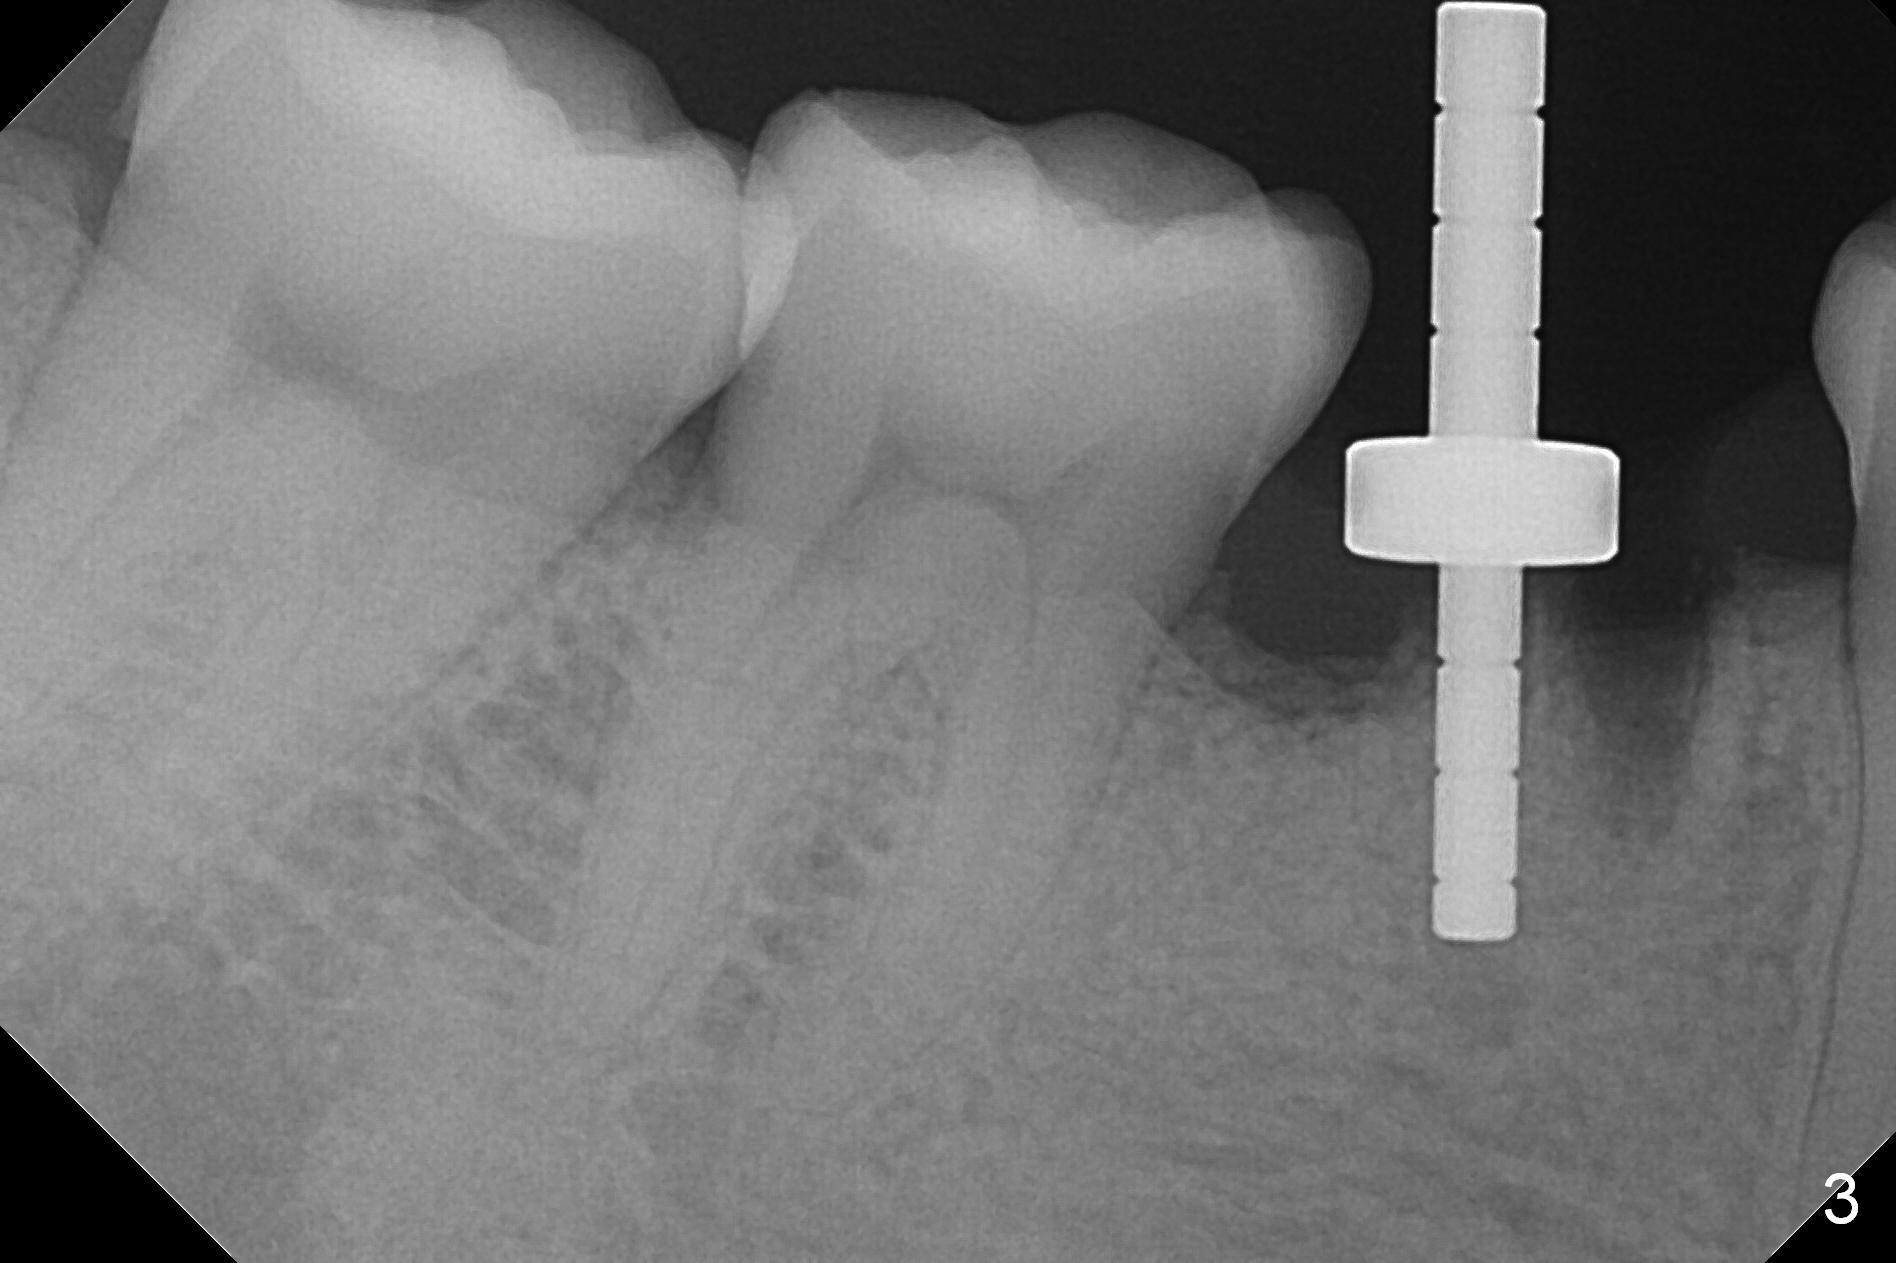

The lower 2nd primary molar has buccal furca lesion (Fig.1 *) with the thin buccal plate (Fig.2). Osteotomy is initiated in the sloped septum (Fig.3). After use of Magic Drill (MD) 3.3 mm for 13 mm and MD 3.8 mm for 11 mm, placement of a 4x11 mm IBS implant meets resistance because of the dense bone (Fig.4-6, red dashed line: Mental Loop) with final insertion torque >50 Ncm. After placement of a 6x4(3) mm abutment and autogenous bone in the remaining shallow sockets (Fig.6), a provisional is fabricated (Fig.7). Finally periodontal dressing is applied. Impression is taken 3 months postop (Fig.8). Buccal infection develops 2 weeks post cementation (Fig.9). When the crown/abutment is removed, there is no residual cement. The implant threads can be felt through the fistula. After soft tissue debridement and copious irrigation, Arestin is placed in the fistula. The latter disappears 15 days post debridement. The patient feels better and moves out of state. It appears that early periimplantitis develops because of the preexisting buccal furca lesion and failure to place the implant deep. The implant will be placed deep after loosening a little (since there is apical space (Fig.8 white line)) or removed, truncated at the apex and placed lower than the buccal crest.